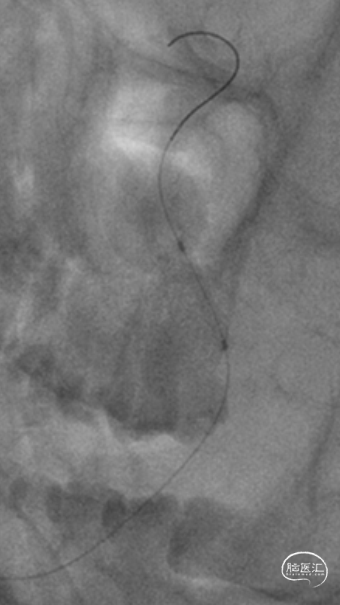

临床上常遇到基底动脉近端闭塞,后交通发达,远端存在前向后代偿病例。部分患者早期桥脑小片状梗死,NIHSS非常低,但容易在数天内逐渐缓慢进展。请问此类患者的介入时机如何把握?

举例图片,非上述病例患者